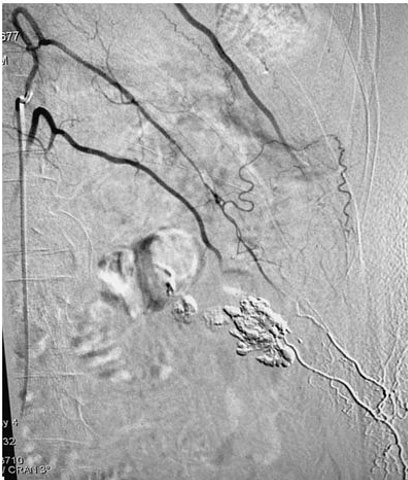

Selective cannulation of the lumbar artery was attempted but it failed due to acute angulation. Cannulation of the lumbar artery at the L1 level was done using a Sim catheter. Super selective angiographic runoff was taken with a progreat microcatheter. It showed filling of the lower L2 level lumbar artery through distal lumbo-limbar collateral vessels and confirmed the pseudoaneurysm and left lumbo-renal venous fistula. Because of difficult anatomy glue embolization of the fistula was done using glue: lipiodol mixture (16% glue). Post-procedure angiogram showed closer of fistula and contrast extravasation (Figure 3).

Figure 3: Post-embolization disappearance of aneurysm and AVF.